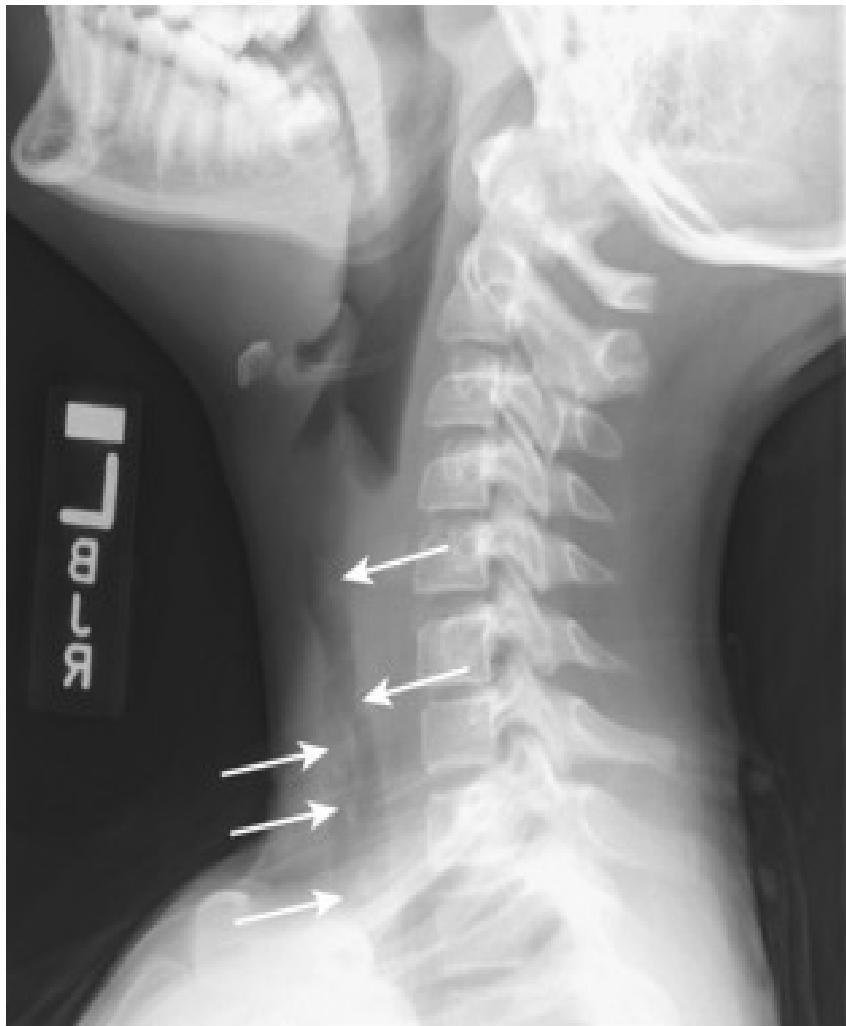

- Soft-tissue Lateral Neck Radiographs:

- Portable if possible.

- Positive in 80% of cases.

- Feature: An enlarged epiglottis protruding from the anterior wall of the hypopharynx (the “thumb sign”).

- Other findings: Thickened aryepiglottic folds, loss of vallecular air space, distended hypopharynx.

- X-ray: Look for the thumbprint sign.